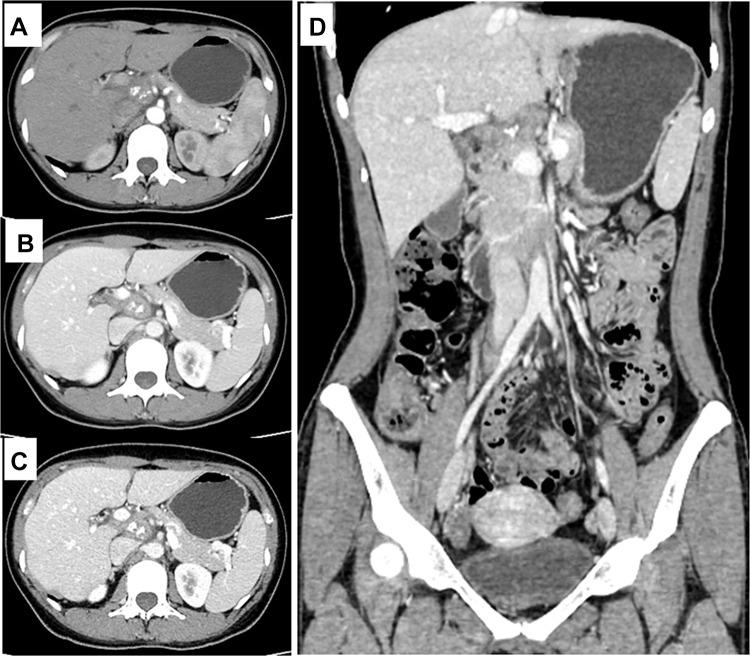

The special location of abdominal tuberculosis makes it difficult for biopsy, while its clinical and imaging characteristics make it indistinguishable from tumors. Here, we report a female patient that was initially misdiagnosed with pancreatic cancer, but eventually correctly diagnosed with tuberculosis in the celiac lymph nodes using F-FDG PET-CT. She was 38 years old. Her main complaint was "deep abdominal pain and discomfort for nearly a month", accompanied by nausea and vomiting. Diagnosis of pancreatic tumors or enlarged lymph nodes was initially made based on CT scan results. Abdominal MRI revealed enlarged lymph nodes. F-FDG PET-CT imaging revealed a soft-tissue mass about 2.8 cm in diameter in the hepatic hilar area with a maximum standardized uptake value (SUV) of 9.4, and delayed imaging measured the SUV at 12. Enhanced CT showed no vascular envelopment in the mass. Based on these results, the patient was diagnosed with tuberculosis in the celiac lymph nodes. Her tuberculin test was strongly positive. After 5 months of antituberculosis treatment, the mass had reduced to about 1.5 cm in diameter and SUV reduced to 8.1, as demonstrated by F-FDG PET-CT imaging. Abdominal lymph-node tuberculosis is easy to misdiagnose, but timely F-FDG PET-CT imaging combined with tuberculin testing may reduce misdiagnosis and mistreatment.